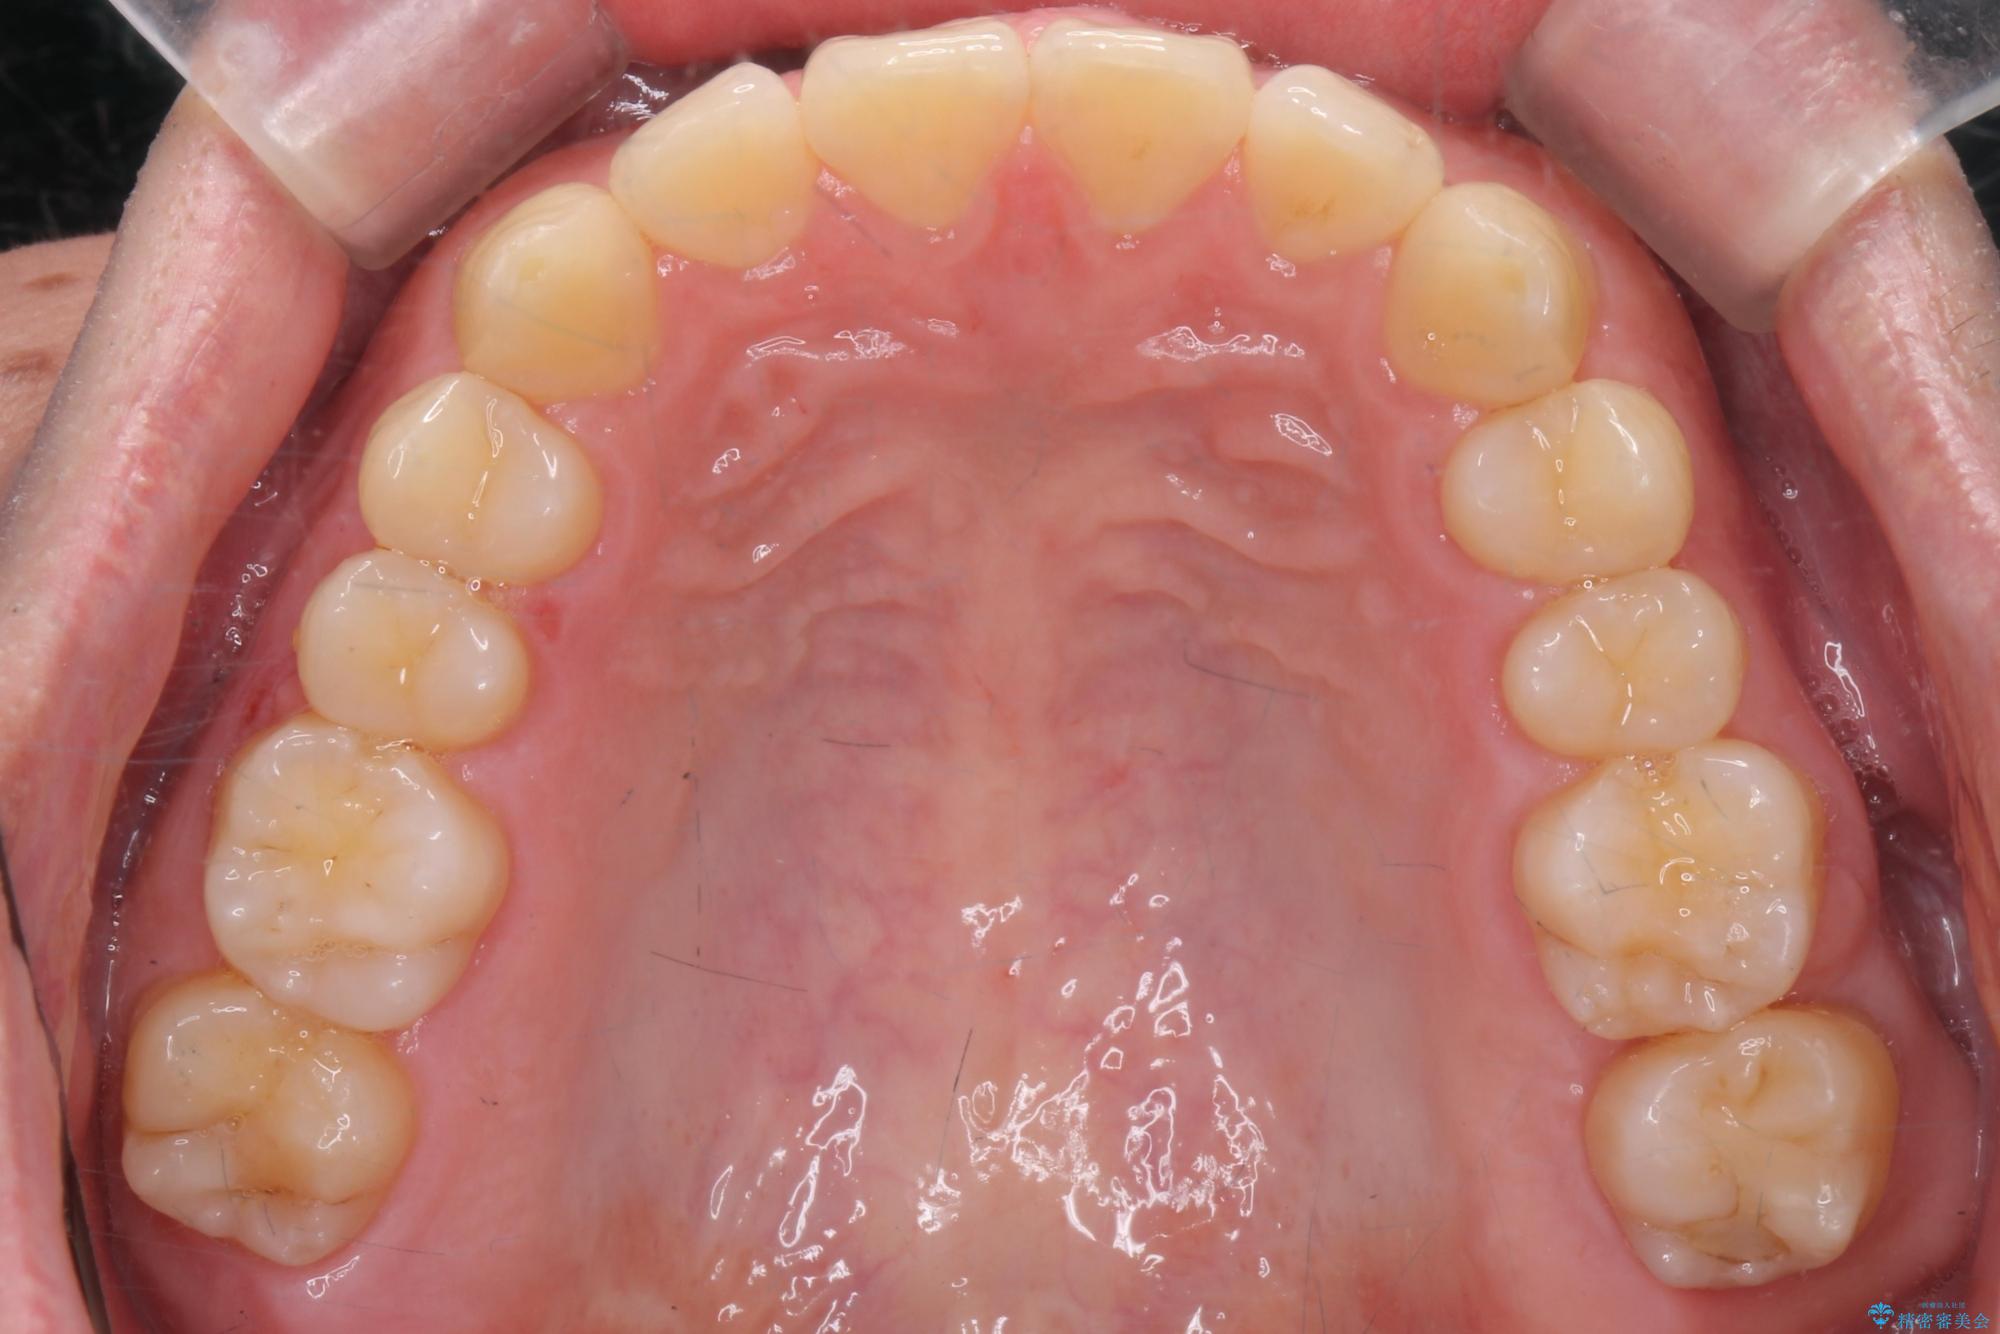

左上の奥歯がシザーバイトがありました。

部分矯正を行いシザーバイトを改善した後、インビザラインで歯列を整えました。

シザーバイトは歯と歯が噛み合っていないのでしっかり噛めるように処置をする必要があります。

歯のがたつきが改善され大変お喜びいただけました。